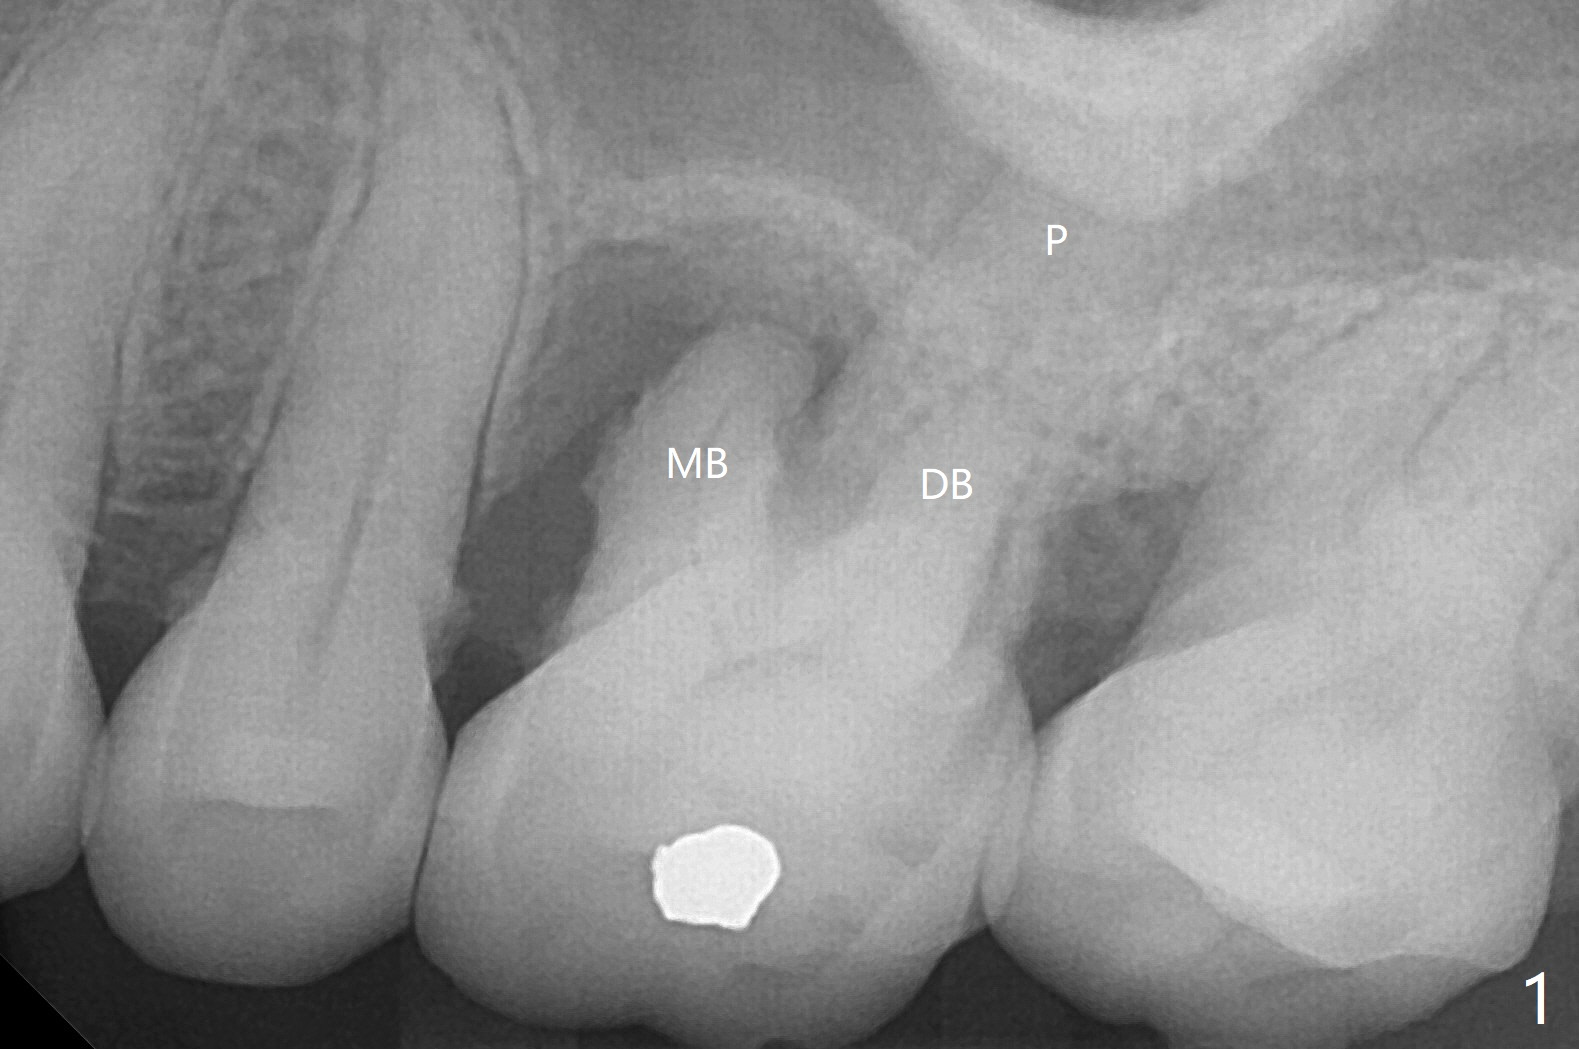

67岁女深洗后突然回来要求拔除左上六(图一),颊侧红肿,流脓,牙周袋深(图二B),经过多番劝导,终于图一植骨,由于时间仓促,使用合成血小板生长因子(GEM21S,而不是PRF))与皮质骨(125μm – 850μm)以及皮松质骨(500μm – 1,000μm)调拌,放置于巨大吸收融合颊侧牙槽窝(图三*(无颊侧骨板)(使用condenser)),而腭侧牙槽窝没有明显破坏(图一P),放置Osteogen Plug(一种骨胶原, 图三 O)。牙槽窝口放置胎盘膜(BioXclude),使用4/0 PGA缝线。傍晚病人已经 没有肿痛了。术后十三天牙周敷料脱落,伤口愈合良好。三天后病人又回来复诊(图四),折线后,虽然伤口愈合,骨粉好像填的不够多(图五),或者丢失。树脂敷料可能取得更好的结果。